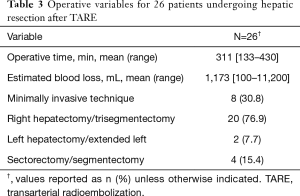

Surgical details are noted in Table 3. Eleven (42.4%) patients underwent additional resections including bowel resection (n=4, 15.4%), portal vein resection (n=2, 7.7%), diaphragmatic resection (n=2, 7.7%), extrahepatic bile duct resection with Roux-en-Y reconstruction (n=2, 7.7%), and right adrenalectomy (n=1, 3.8%). A staged resection was performed in one (3.8%) patient with bilobar colorectal metastasis who underwent left lateral hepatectomy prior to right hepatectomy as has been previously described (43). The mean time from TARE to surgery was 235 days (107–636 days).